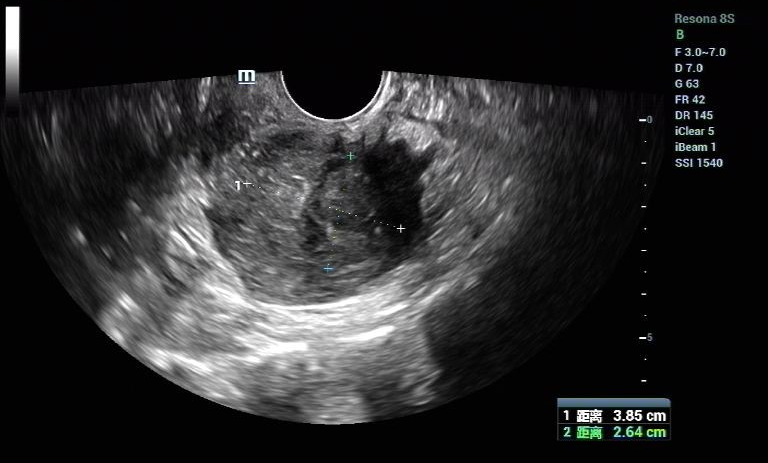

患者女,28岁,2021-06-07于青岛市妇女儿童医院就诊。 主诉:进行性痛经加重3年余。 现病史:患者月经初潮即有经期下腹痛,无需口服止痛药物。3年前痛经渐进性加重,目前经期腹痛VAS评分8分,伴恶心呕吐、肛周坠胀感。伴有非经期腹痛,VAS评分4分,持续4-5天,有深部性交痛。月经周期、经期及经量较前无明显改变。我院就诊超声提示:子宫后壁探及低回声结节,大小46mm*56mm*42mm,考虑子宫肌瘤。患者有明确生育要求,为求进一步治疗,门诊以“子宫腺肌病?子宫肌瘤?”收入院。患者自发病以来,神志清,精神可,饮食正常,经期夜间睡眠欠佳,体重较前无明显增减。 既往史:体健,否认慢性病及传染性疾病病史,否认外伤史,否认输血史,否认食物、药物过敏史。 月经及婚育史:既往月经规律,周期28-30天,经期5-6天,末次月经:2021-05-24。G1P0A1,2021年4月孕11周“稽留流产”行药物流产1次。 家族史:无特殊。 体格检查:T36.2℃,P77次/分,R18次/分,BP101/67mmHg,身高160cm,体重56kg。疼痛评分:0分。心、肺、腹部查体无异常。 专科查体: 妇科查体:外阴发育正常,阴道畅,宫颈光滑,子宫后位,增大如孕2月,固定、活动差,无压痛,双侧附件区未及异常。三合诊:左侧骶韧带触及触痛结节。 辅助检查: 2021-06-03 B超:子宫后位,宫体大小正常,形态规则,肌层内回声欠均匀,后壁肌层探及低回声结节,大小约46mm*56mm*42mm,边界清。宫腔内膜受压前移,厚10.1mm。宫颈形态正常。左侧卵巢探及液性暗区,大小约39mm*29mm,透声好,右侧卵巢大小正常。右侧附件区未见明显异常。 2021-06-07 肿瘤指标:糖类抗原CA19-9 52.21U/ml;糖类抗原CA125 112.9U/ml ↑; 2021-06-07 MRI提示:子宫后壁子宫腺肌病、盆腔子宫内膜异位症? 初步诊断: 2.盆腔子宫内膜异位症 3.不良孕产史 1.2021-06-08在镇静镇痛下行聚焦超声消融手术(FUAS)治疗。术后增强核磁检查提示子宫后壁腺肌病灶内无灌注区,子宫内膜及浆膜血流灌注正常。 2.2021-06-22术后第一次月经来潮,痛经较前减轻,VAS评分2-3分。术后辅助GnRh-a治疗3周期辅助治疗,同时口服钙片补钙治疗,用药期间闭经,无腹痛等不适。 3.GnRh-a治疗3周期后,2021-09-08复查B超:子宫后位,宫体大小正常,形态规则,肌层内回声欠均匀,后壁肌层探及高回声团,大小约38mm*37mm*26mm,边界清,内见少许血流信号。宫腔内膜受压前移,厚4.1mm。宫颈形态正常。双侧卵巢大小正常。双侧附件区未见明显异常。 4.2021-11-22月经复潮,经量正常,痛经VAS 2分,月经第5天开始口服地屈孕酮20mg QD,每月经周期20天,建议试孕半年。 5.2022-04-27随访复查,LMP:2022-02-24,停经9周,B超:子宫后位,体积增大,形态饱满,被膜光滑,后壁肌层回声不均匀,内见低回声区,较大范围约35mm*26mm,宫腔内见大小约32mm*31mm*24mm妊娠囊,张力可,内见胎芽,纵径22.4mm,心管搏动规律,妊娠囊下方探及不规则液性暗区,范围约21mm*8mm。双侧附件区未见明显异常。继续口服地屈孕酮10mg q8h保胎治疗。孕期进展顺利,2022-11-25外院足月剖宫产1女婴,体重3300g,Apgar评分10分-10分。 子宫内膜异位症和子宫腺肌病是妇科常见疾病。除了引起疼痛和月经改变,越来越多的证据表明,这两种疾病对女性的生殖功能有重要影响。临床可表现为不孕不育和流产等,尤其是早期流产[1]。 本例患者B超提示“子宫肌瘤”可能,但后续评估更符合子宫腺肌病。弥漫性子宫腺肌病的超声检查准确性较高,但子宫腺肌瘤超声表现与子宫肌瘤相似,临床诊断需要结合患者的症状、CA125水平综合判断。相比超声,磁共振检查对子宫腺肌病的分型更有优势,也更容易发现合并的盆腔子宫内膜异位症。后位子宫的后壁腺肌病灶往往合并子宫直肠陷凹的内异病灶,本例患者即属于该情况,治疗策略应兼顾两种疾病并同时考虑患者的生育需求。 针对子宫腺肌病,传统的病灶切除手术对子宫损伤较大,合并盆腔子宫内膜异位症时,手术操作也较困难,所以对于有生育需求的患者选择手术治疗需要相当慎重。聚焦超声消融术(HIFU)可选择性消融子宫腺肌病病灶、使病灶缩小,同时保护子宫完整性,从而达到减轻症状、缩小病灶、改善生育的目的[2]。但无法同时消融盆腔子宫内膜异位病灶,需要联合药物综合治疗。 子宫腺肌病和子宫内膜异位症的慢病管理理念已逐渐被认可,药物治疗是基石。而目前一线用药促性腺激素释放激素激动剂、地诺孕素等均会抑制排卵,有生育需求的患者备孕时需要停药。而停药后的试孕期病灶复发和进展风险较高,从而影响妊娠几率。地屈孕酮10-20mg/d可缓解内异症痛经,不抑制排卵,兼顾子宫腺肌病和盆腔子宫内膜异位症患者的治疗和备孕。此外,对于疑有黄体功能不足者黄体期使用地屈孕酮还可能提高自然受孕率,备孕期周期性用药副作用低,安全性高。 子宫腺肌病不仅可导致患者的生育力低下,诸如排卵障碍、不孕、流产、早产、死产、胎儿生长受限等,还可导致妊娠期母亲并发症如剖宫产率增加、子痫前期、前置胎盘及胎盘早剥等[3],一旦妊娠应更加积极的给予保胎治疗和严密随访,积极补充孕酮以抑制子宫平滑肌收缩,尽可能提高活产率。 子宫腺肌病和子宫内膜异位症具有类似的发病机制,也常常合并存在,严重影响女性的生殖健康。针对两种疾病的治疗应规范化、个体化、微创化。给予规范用药或手术治疗,减灭和消除病灶,减轻临床症状的同时,应充分考虑患者的主要诉求、年龄和生育需求,尽可能选取创伤小的治疗方式。重视患者全生命周期的管理,早诊早治、促进生育、长期管理预防复发,避免反复手术带来的创伤,定期随访,警惕恶变。 该患者28岁,痛经伴非经期腹痛,临床诊断符合子宫腺肌瘤合并子宫内膜异位症。既往不良孕产史,有明确生育需求,具有治疗指征。针对后壁子宫腺肌瘤传统手术方式对子宫损伤较大不利于患者后续妊娠,康医生选择了聚焦超声消融术治疗缩小子宫腺肌病病灶,减轻患者痛经并改善子宫形态,有利于提高妊娠几率。 子宫腺肌病和子宫内膜异位症在年轻患者中复发几率极高,可谓“不死的癌症”,当患者又有生育需求时,如何兼顾治疗和生育确实给我们提出了较高的要求。该患者在停用GnRh-a后月经来潮,备孕期间给予口服地屈孕酮稳定病灶、改善痛经,同时不会影响下丘脑-垂体-卵巢轴(HPO轴)而抑制排卵,还能提高自然受孕几率,可谓一举两得。 患者服用地屈孕酮3个月后便顺利妊娠,体现了治疗的有效性。更难能可贵的是,康医生重视子宫腺肌病患者的孕期管理,妊娠后继续给予口服地屈孕酮积极保胎,抑制子宫平滑肌收缩,也体现了将子宫腺肌病患者作为高危孕产妇管理的治疗理念。 参考文献: